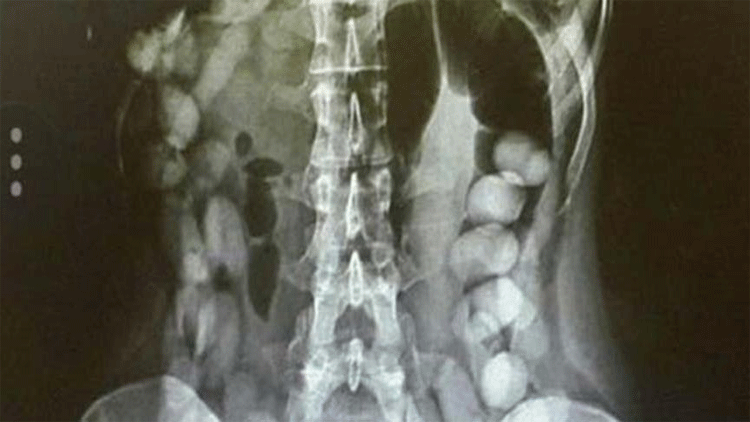

Denizli Devlet Hastanesi’ne götürülen O.R.’nin çekilen röntgen filminden midesinde, şeffaf poşetlere sararak yuttuğu 5 poşet halinde eroin olduğu tespit edildi.

Hastanede midesindeki uyuşturucu çıkarttırılan O.R.’nin yuttuğu eroinin 2.5 gram olduğu belirlendi.